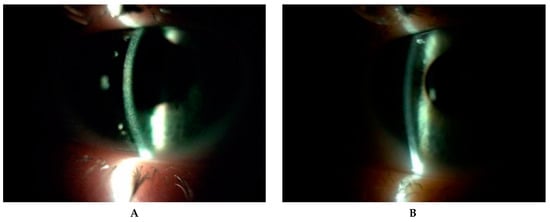

All patients underwent conjunctival examination to assess the presence of cystine crystals and level of conjunctival hyperemia (Figure 1 and Figure 2). The degree of corneal crystal deposition was assessed using Gahl’s corneal cystine crystal (CCC) score on slit lamp examination and photographs on a scale 0–3, with steps of 0.25 (based on opacity, density and number of crystals) during first visit (FV) and last visit (LV).

Figure 2. Slit-lamp images (10–25×) of posttransplant cornea in a patient (P7) with an infantile form of cystinosis. (A) Diffused cystine crystalsin right eye. (B) Peripheral corneal neovascularization with crystal deposits in the left eye after keratoplasty. (C) Cystine crystals are visible in the host cornea, in wide slit beam and (D) narrow slit beam in left eye.

Figure 6. Corneal cystine crystals in slit lamp (10×) before administration of hospital formulated 0.5% cysteamine (A) and one year after application of 0.55% Cystadrops (B) in patient 2.